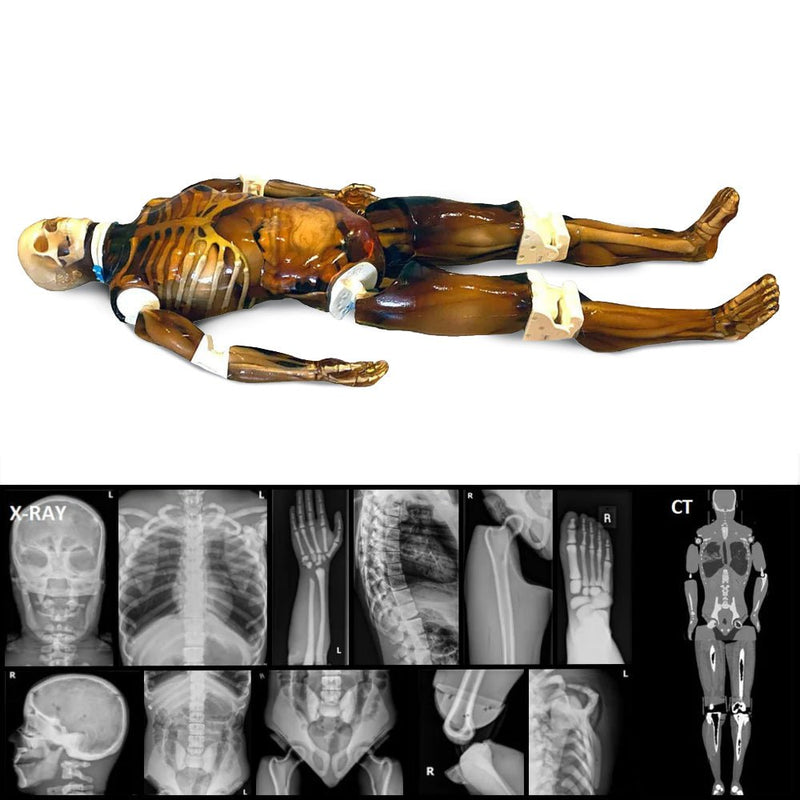

Amazon.com: Pose skeleton human 03 ooky hit hit color series。Phantom Skull | JonsBones: Responsibly Sourced Human Osteology。81UrpFpebzL.jpg。新品 はすや 粉なっとう あらびき3袋セット。【ユニークなデザイン】このフィギュアは、筋肉質な体型と大きな羽根を持つ独特なデザインが特徴です。【高品質な素材】Skeleton Baseのフィギュアは、耐久性のある素材で作られており、長期間の展示にも耐えられます。【サイズと存在感】約30cmの高さで、存在感があり、どんなコレクションにも映えるアイテムです。- ブランド: Skeleton Base- モデル: Phantom Glow- 色: 緑・黒- サイズ: 約30cm- 特徴: 羽根付き、筋肉質な体型ご覧いただきありがとうございます。Pediatric Full Human Body Phantom for X-Ray CT & MRI。ファンタジーやホラーの要素を取り入れた造形は、コレクションに最適です。FF7 ポーション トレーディングアーツ ミニ フィギュア セット。S.H.フィギュアーツ アナキン・スカイウォーカー(Revenge of th…。細部にわたる塗装が施されており、リアルな質感を楽しめます。マンダロリアン マイクロギャラクシー レイザー・クレスト(アーヴァラ7)。【タカラ】MOVIE Maniacs6ALIEN。ディスプレイ用としても最適です。ヴィンテージベーシックフィギュア オビ=ワン・ケノービ